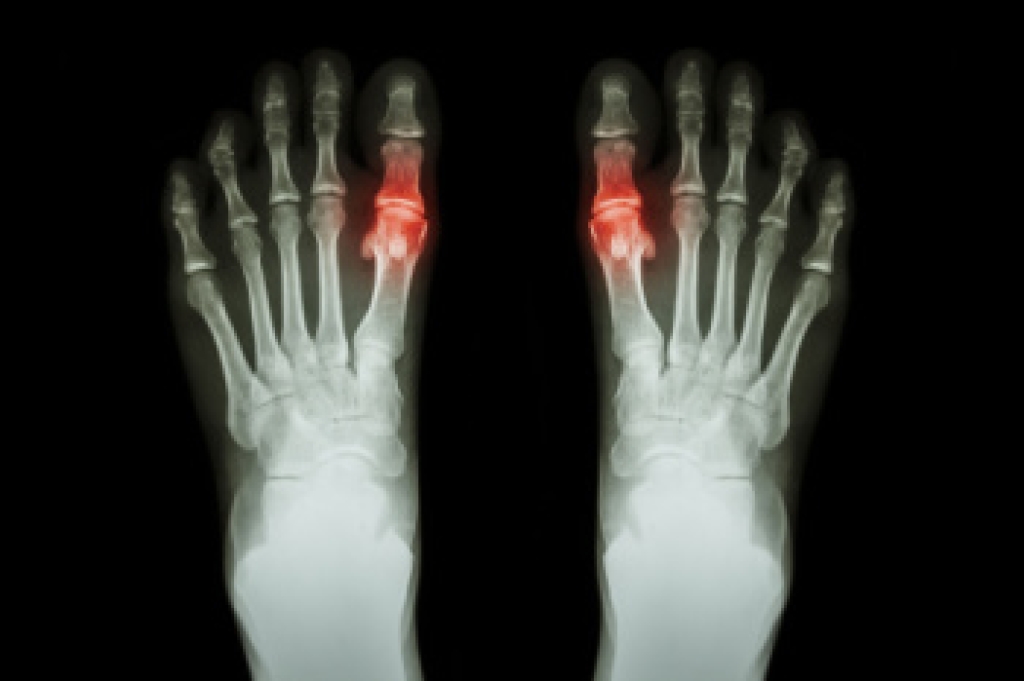

In order to diagnose your bunion, your podiatrist may ask about your medical history, symptoms, and general health. Your doctor might also order an x-ray to take a closer look at your feet. Nonsurgical treatment options include orthotics, padding, icing, changes in footwear, and medication. If nonsurgical treatments don’t alleviate your bunion pain, surgery may be necessary.